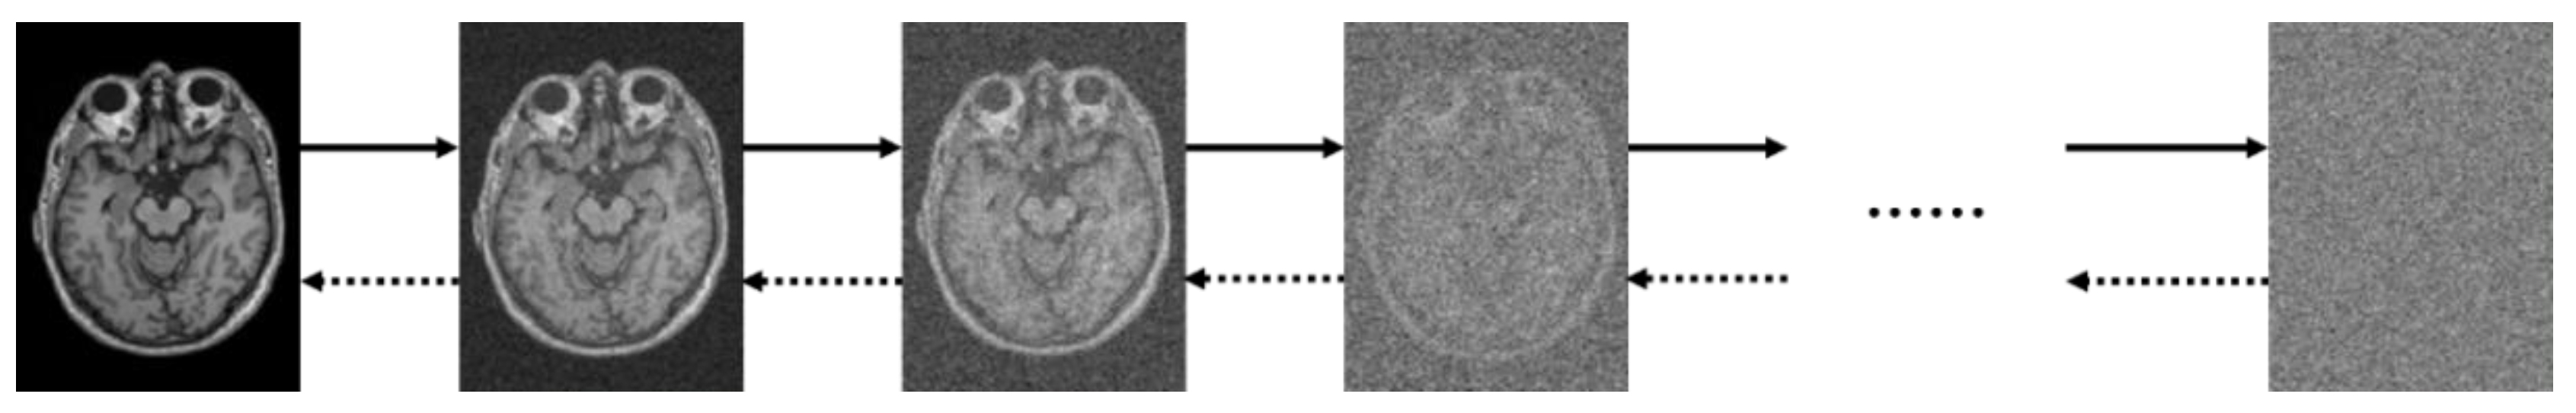

4.3. Diffusion Model